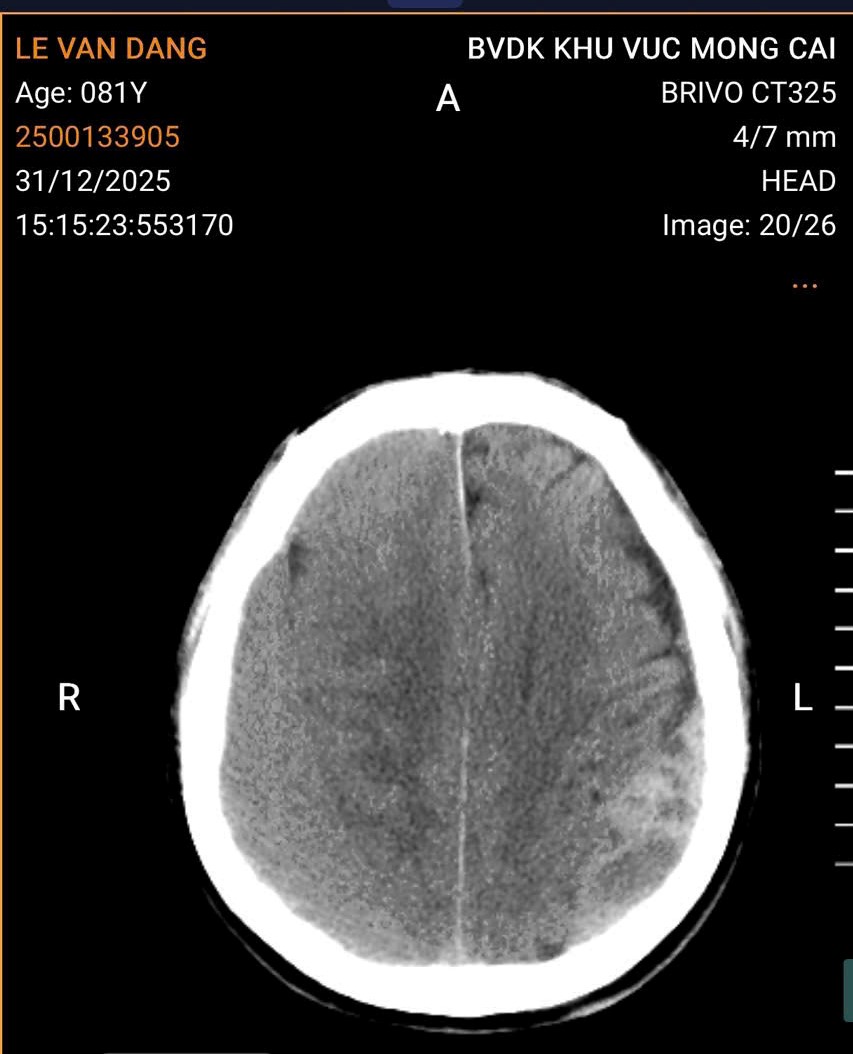

Qua thăm khám lâm sàng và thực hiện chụp cắt lớp vi tính sọ não, các bác sĩ phát hiện bệnh nhân bị tụ máu dưới màng cứng bán cấp hai bên với số lượng nhiều. Đây là tình trạng bệnh lý nguy hiểm, cần can thiệp phẫu thuật cấp cứu. Bệnh viện đã tổ chức hội chẩn với chuyên khoa Ngoại Thần kinh – Bệnh viện Đa khoa tỉnh Quảng Ninh, đồng thời hoàn thiện các xét nghiệm cần thiết và thống nhất chỉ định phẫu thuật lấy khối máu tụ trong sọ cho người bệnh.

Hình ảnh chụp cắt lớp vi tính sọ não